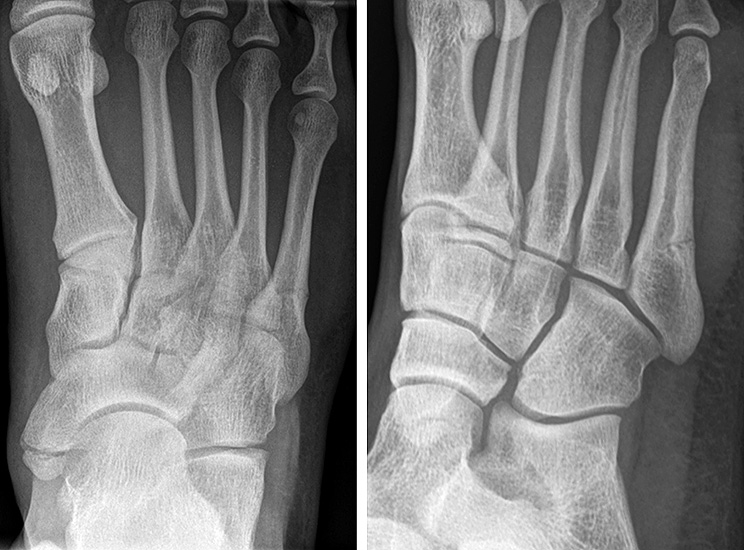

Abbildung 2 A+B

Akzessorische Knochen im Bereich der MT V Basis können als Frakturen fehlgedeutet werden. Hier sind insbesondere das Os vesalianum (zweiter Ossifikationskern des MT V, im Ansatzbereich der Peronus brevis Sehne) sowie das Os peroneum (Akzessorischer Knochen im Sehnenverlauf der Peronaeus longus Sehne, lateral des Os cuboideum) zu nennen 10.

Ein detailliertes Verständnis der anatomischen Gegebenheiten in Verbindung mit den oben beschriebenen Klassifikationen ist für die Behandlungsentscheidung wichtig. Die in Abbildung 2A dargestellten Sehnen, Muskeln und Bänder stabilisieren einerseits die Basis des MT V, zum anderen kann der Muskelzug auch zu einer sekundären Dislokation der Fragmente führen bzw. eine Pseudarthrose begünstigen. Das metadiaphysäre und diaphysäre MT V ist weniger rigide verspannt als die MT V Basis. Bei Frakturen im metadiaphysären Übergang (Lawrence und Botte Zone III) kann es also aufgrund des relativ mobilen Schaftes zu stärkeren interfragmentären Bewegungen kommen. Diese haben wiederum einen negativen Einfluss auf die Knochenheilung.

Auch die Blutversorgung variiert innerhalb des MT V (Abb. 2B). Die proximale Metaphyse wird von extraossär über ein Netz aus Perforansgefäßen (Seitenäste der A. tarsea lateralis) versorgt. Die Diaphyse wird intraossär von einer A. nutricia versorgt. Der metadiaphysäre Bereich (Lawrence und Botte Zone III) liegt zwischen diesen beiden Versorgungsgebieten und ist daher relativ weniger durchblutet. Eine eingeschränkte Blutversorgung hat wiederum einen negativen Einfluß auf die Frakturheilung 111213.